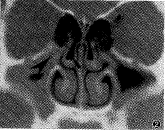

图1 燕尾箭头示Haller气房, 长三角箭头分别示钩突与筛漏斗

以往CT检查多采用轴位和冠状位2个方向扫描,甚至有的首先采用轴位扫描。笔者认为应 首先采用冠状位扫描,若后组副鼻窦未发现异常,则无需进行轴位扫描。在后组鼻窦发现病 变并考虑手术治疗时,再补充轴位检查,因后者只对显示蝶筛隐窝或了解后组鼻窦与视神经 骨管关系时有用。这与赵昕等意见一致,可以节省时间和费用。本组资料表明,一组包括蝶 窦的冠状位图像,足以判断后组鼻窦有无明显病变和了解OSCO区的细节,而这些结构多显示 于眼球后极的附近层面上(图1)。

不同类型的副鼻窦炎表现受累部位和炎症范围不同,正确 判定是制定治疗方案的主要依据。钩突和筛漏斗是一个可显示的明确标志。在冠状位上,钩突表现为一个起自下鼻甲根部(筛 突)向上、向内弯曲的薄骨片(图1),表面覆以薄粘膜,构成筛漏斗的内壁;其外壁即眼 眶的内下壁,也有粘膜覆盖,两者构成一长三角形气腔,下通上颌窦,上与中鼻道相通,向 后通半月裂。本组资料测得其骨管宽度在3~4mm之间,气道宽度不小于2mm。该处局限性闭 塞或狭窄,伴有同侧上颌窦炎,而其他前组副鼻窦正常,是诊断漏斗型的基础,若保守治疗 无效,行漏斗扩大术和/或钩突切除术是可行的。有时病侧上颌窦只一部分混浊或粘膜肥厚 ,而另一部分正常,这可能是上颌窦副窦口未受侵的缘故,因筛漏斗主要引流后部上颌窦的 分泌物。

筛泡位于前组筛窦之后,是中组筛窦的较大气房,左右各 一,大致对称。筛泡的内下缘突向中鼻道外上部,构成中鼻道外上壁的一部分,其内下方小 孔直接开口于中鼻道,或经筛漏斗上方与中鼻道相通,是在冠状位上易于识别的结构,其正 常大小尚无统一认识。本组所谓“过大”,是按一侧横径大于对侧1/3时统计的(图1,右侧 筛泡),过大可致中鼻道上部狭窄。而半月裂是筛泡下方的一个前后走行的狭窄裂沟,沟内 前上方有额窦开口,向后依次为前、中组筛窦开口,后部有上颌窦开口。此沟在冠状位上不 易完全显示,其部分可显示于筛漏斗的稍后层面上,呈对称缺口(图3)。其上方为筛泡,下 方为钩突后部。若此区和筛泡同时混浊,并伴有前组副鼻窦不同范围的炎症,是诊断OSCO型 前组鼻窦炎的基础。此型临床上多采取开筛术和/或兼作窦口扩大术、病灶清除术处理。

Bolger等[6]强调OSCO区的解剖变异在副鼻窦炎中的作用;国内赵昕等[3] 也注意到变异与本症的关系,但皆未提供正常组资料。如附表 所示,在正常组与病变组之间似无统计学意义。笔者认为这些变异可能是解剖上较为常见的 现象,至少不是构成本组病变的主要因素。我国北方气候寒冷干燥,这一外部环境和个人体 质因素(如过敏等)可能是主要原因。不可否认,严重的变异畸形会导致窦口引流不畅,增加 感染机会。在本组资料中,中隔明显突向健侧,大筛泡、Haller气房(图1)出现于健侧,似 乎也支持上述观点。